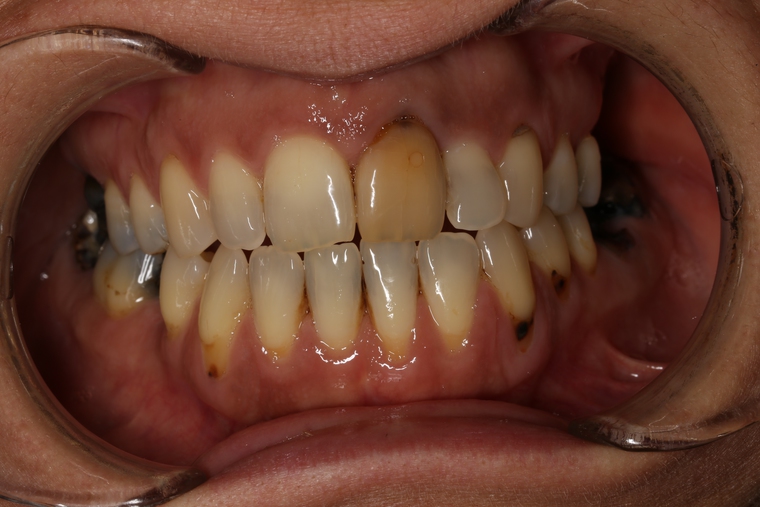

Ein Tätigkeitsschwerpunkt unserer Praxis in Salzburg ist die Implantologie. Wenn ein Zahn fehlt oder entfernt werden muss, sollte immer die Möglichkeit der Implantation im Vordergrund stehen. Ein Implantat verhält sich von den Eigenschaften genau so wie ein natürlicher Zahn. Egal ob nur ein einzelner Zahn vom Zahnarzt ersetzt werden muss oder ein ganzer Kiefer mit festsitzendem Zahnersatz versorgt werden soll, wir finden für Sie eine Möglichkeit, auch wenn die Voraussetzungen ausweglos erscheinen. Wenn möglich versorgen wir unsere Patienten mit Keramikimplantaten. Diese sind immun-neutral und können sehr oft direkt bei der Zahnextraktion eingesetzt werden. Für unsere Patienten ist daher meist nur ein operativer Eingriff notwendig!